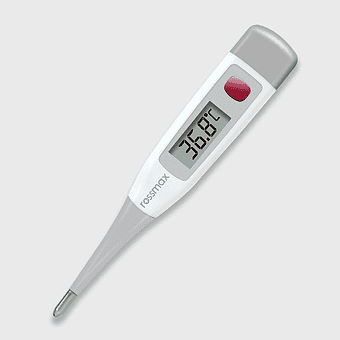

digital thermometer 37.0, medical device temperature measurement, celsius temperature reading, health care tool, electronic medical instrument, body temperature monitor, digital health equipment -

digital thermometer Celsius, temperature measurement tool, human body temperature gauge, celsius temperature scale, medical temperature reading, clinical thermometer design, health monitoring device -